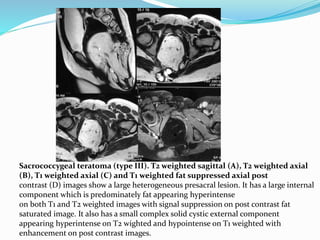

Sacrococcygeal teratoma (type III). T2 weighted sagittal (A), T2 weighted axial

(B), T1 weighted axial (C) and T1 weighted fat suppressed axial post

contrast (D) images show a large heterogeneous presacral lesion. It has a large internal

component which is predominately fat appearing hyperintense

on both T1 and T2 weighted images with signal suppression on post contrast fat

saturated image. It also has a small complex solid cystic external component

appearing hyperintense on T2 wighted and hypointense on T1 weighted with

enhancement on post contrast images.